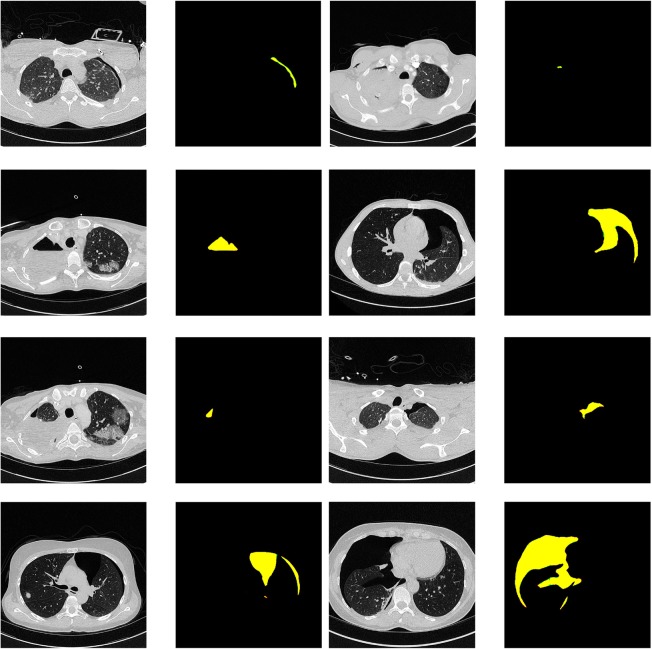

Qualitative segmentation results are shown in Figs. 4 and 5. False-negative cases were observed only in very small pneumothoraxes, in small and thin regions of free air next to chest tubes. False-positive cases were mainly due to panlobular or chest-wall emphysema, bullae, and, in one case, due to misclassification of air inside the main bronchus.

Fig. 4.

Segmentation results. Raw images and corresponding segmentation results. False-negatives (red), false-positive pneumothorax predictions (green), and correct pneumothorax predictions (yellow) The areas of false prediction are very subtle and correspond to a few pixels on the edges of the correct yellow predictions. In the next Figure (Fig. 5), in contrast, the areas of false prediction are shown more prominently

Fig. 5.

Failure cases of segmentation results. Raw images and corresponding segmentation results. False-negatives (red), false-positive pneumothorax predictions (green), and correct pneumothorax predictions (yellow)